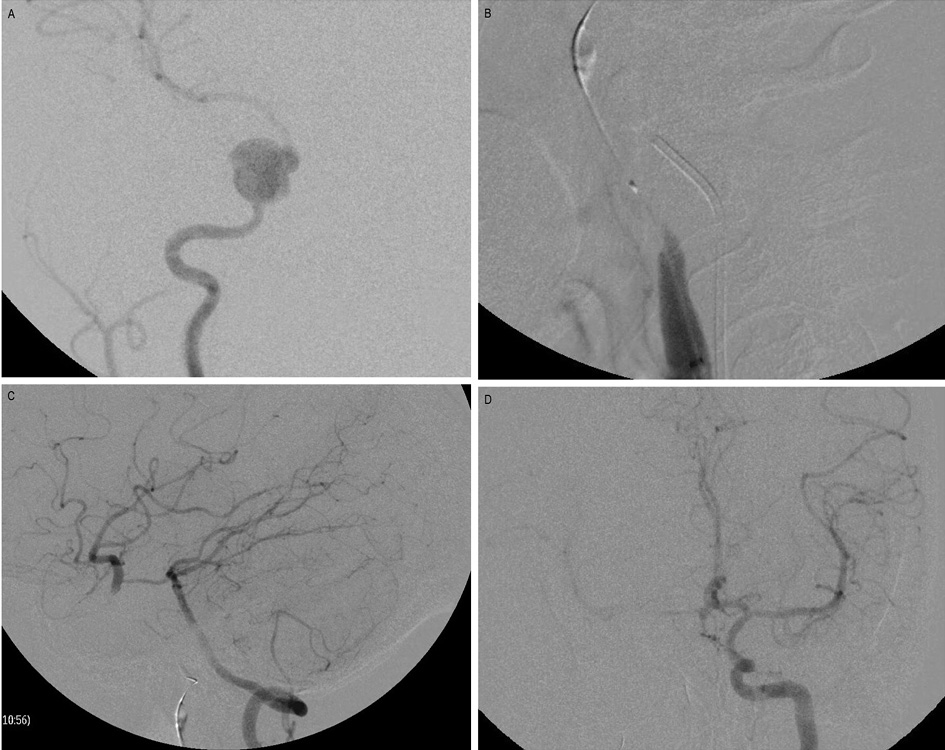

The balloon test occlusion (BTO) was performed before PAO for all patients with proximal intracranial artery aneurysm (Figure1). Under all aseptic precaution and local anesthesia, the common femoral artery was punctured and 80U/kg body weight heparin was injected. A balloon was carefully inflated proximal to the aneurysm and continuous neurologic examination for the motor, sensory, cognition, and cranial nerve functions were performed for 20-min. The PAO was performed only when the patient tolerated the balloon occlusion test without a neurological deficit. During balloon inflation, multiple selective angiograms were performed through the contralateral internal cerebral artery (ICA) and vertebral artery (VA), for demonstration of adequate cross circulation flow.

Figure1. Balloon occlusion test (BTO).

A. Angiography of the right ICA reveals a pseudoaneurysm arising from the right cavernous ICA. B. A balloon is inflated at the right petrous ICA proximal to the aneurysm. C. Angiography of the left vertebral artery reveals good cross circulation through Pcom, filling the right ICA circulation. D. Angiography of the opposite ICA reveals no adequate cross circulation through Acom.